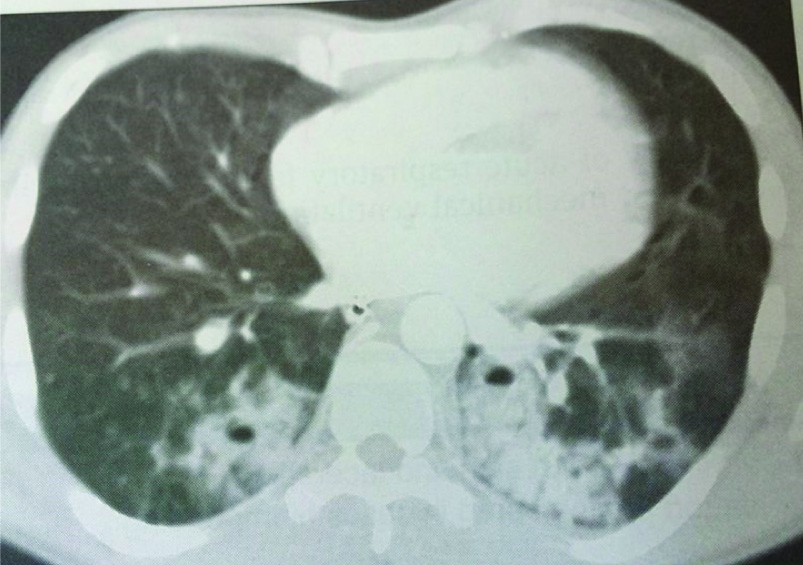

CT scan thorax showing bilateral lung contusions of lower lobes

Chest X-ray is the first investigation for evaluation but CT thorax remains a better choice. Focal or diffuse homogeneous opacification on chest radiograph is the mainstay of diagnosis for lung contusion. The opacification seen with pulmonary contusions is irregular and does not conform to segments or lobes within the lung. Pulmonary contusion is not always immediately apparent radiographically; one-third of patients fail to demonstrate a lesion on the initial chest radiograph [7] and hence often it requires follow-up chest radiograph for confirmation of the diagnosis. In the present study most of the patients had undergone a CT thorax for detail evaluation of thoracic injuries including haemothorax. Cohn et al., [1] has observed that the CT scan of thorax is highly sensitive in identifying the lung contusions and may help in predicting ventilator requirement.